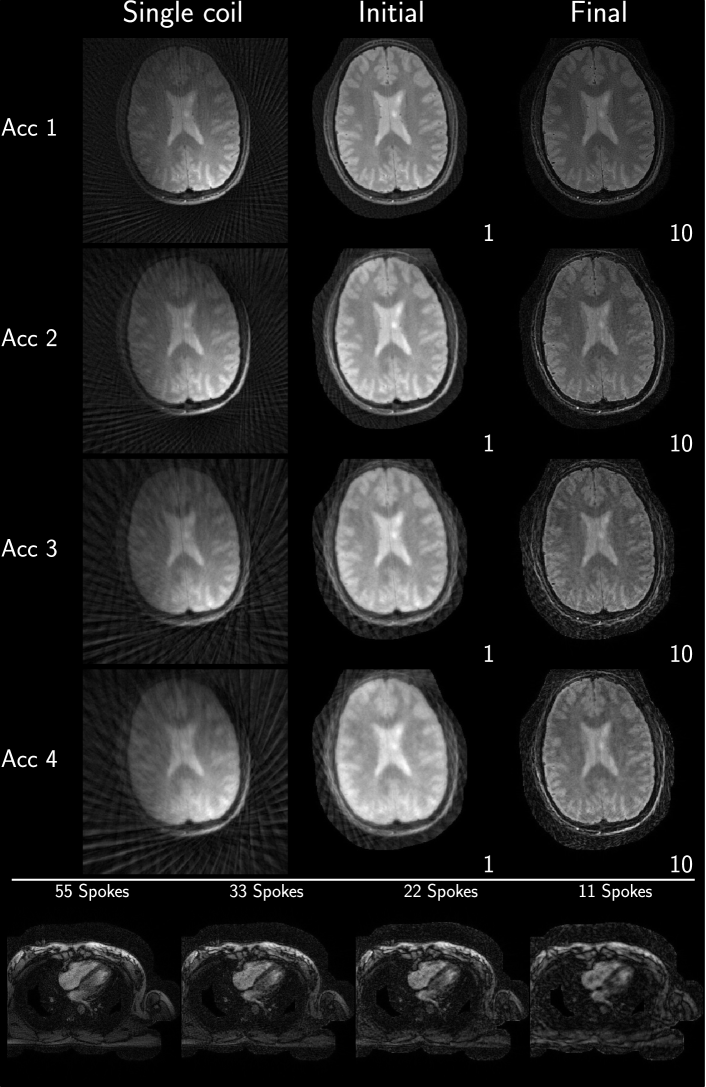

Example reconstruction results for an acceleration factor of 2, showing the image after evaluation of the right-hand-side of equation 3 (Initial) and after convergence of the algorithm (Final), from each submission are given in Figure 2 and Figure 3 for brain and heart data, respectively. All results are displayed with a window width from the minimum to the maximum occurring value in each image. Visually, intensity variations are noticeable owing to the different maximum values, however, contrast between different tissue seems to be similar in all submissions. Some submissions also use different FOVs for the brain (Eindhoven - no cropping, ETH - cropped to 340x340, Stanford - cropped asymmetrical to 300x300 ) compared to the others or different matrix sizes in the same FOV (USC - 256x256 and Utah - 512x512). No major structural differences are observable in the reconstruction except for the case of Eindhoven. The brain reconstruction from KI did neither use Tikhonov regularization nor early stopping, and the k-space was not filtered, resulting in a noisy appearance compared to other submissions. In addition, it shows a slight rotation to the left.

Figure 4: Consolidated reconstruction results using the Python implementation.

Refer to caption

Figure 5: Consolidated reconstruction results using the Matlab implementation.